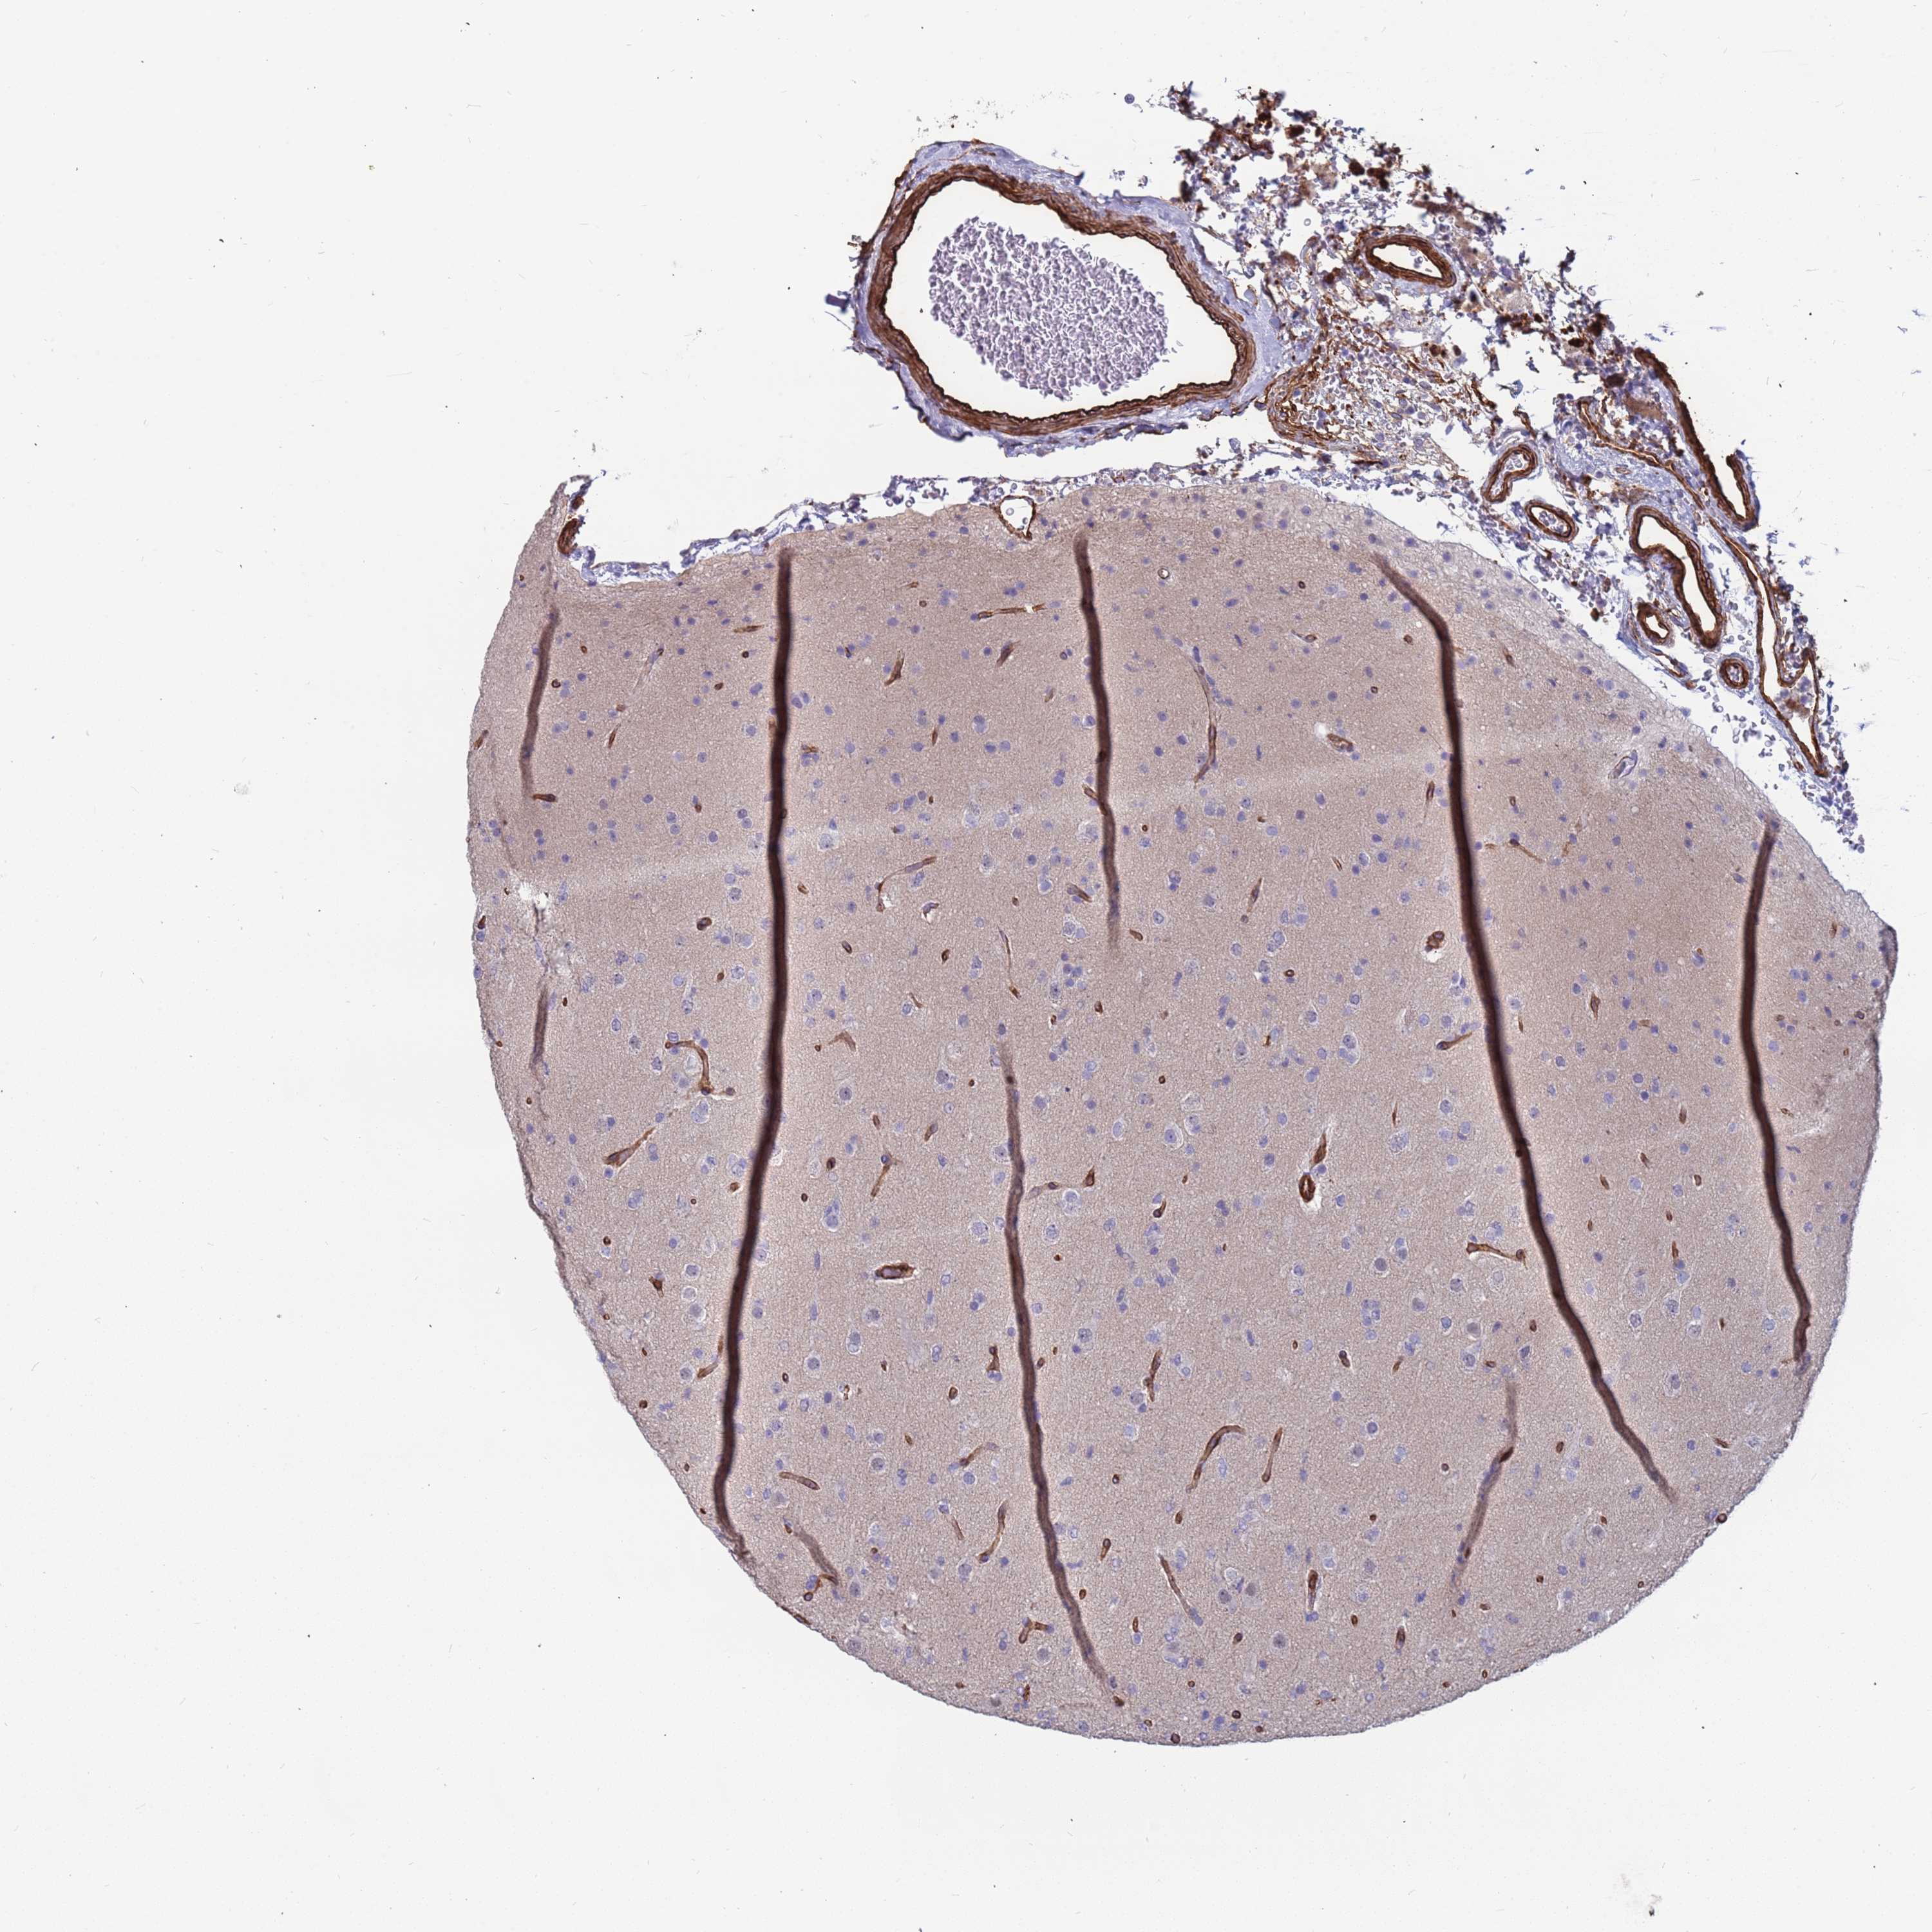

GLIOMA - Protein expressioni

A mouse-over function shows sample information and annotation data. Click on an image to view it in a full screen mode. Samples can be filtered based on level of antibody staining by selecting one or several of the following categories: high, medium, low and not detected. The assay and annotation is described here.

Note that samples used for immunohistochemistry by the Human Protein Atlas do not correspond to samples in the TCGA dataset.

Antibody stainingi

Antibody staining in the annotated cell types in the current human tissue is reported as not detected, low, medium, or high, based on conventional immunohistochemistry profiling in selected tissues. This score is based on the combination of the staining intensity and fraction of stained cells.

Each image is clickable and will lead to virtual microscopy that enables deeper exploration of all samples and also displays staining intensity scores, fraction scores and subcellular localization as well as patient and tissue information for each sample.

Antibody HPA047394

Antibody HPA049890

Antibody HPA049986

Staining

High

Medium

Low

Not detected

Intensity

Strong

Moderate

Weak

Negative

Quantity

>75%

75%-25%

<25%

None

Location

Nuclear

Cytoplasmic/membranous

Cytoplasmic/membranous,nuclear

Glioma, malignant, High grade

Glioma, malignant, Low grade